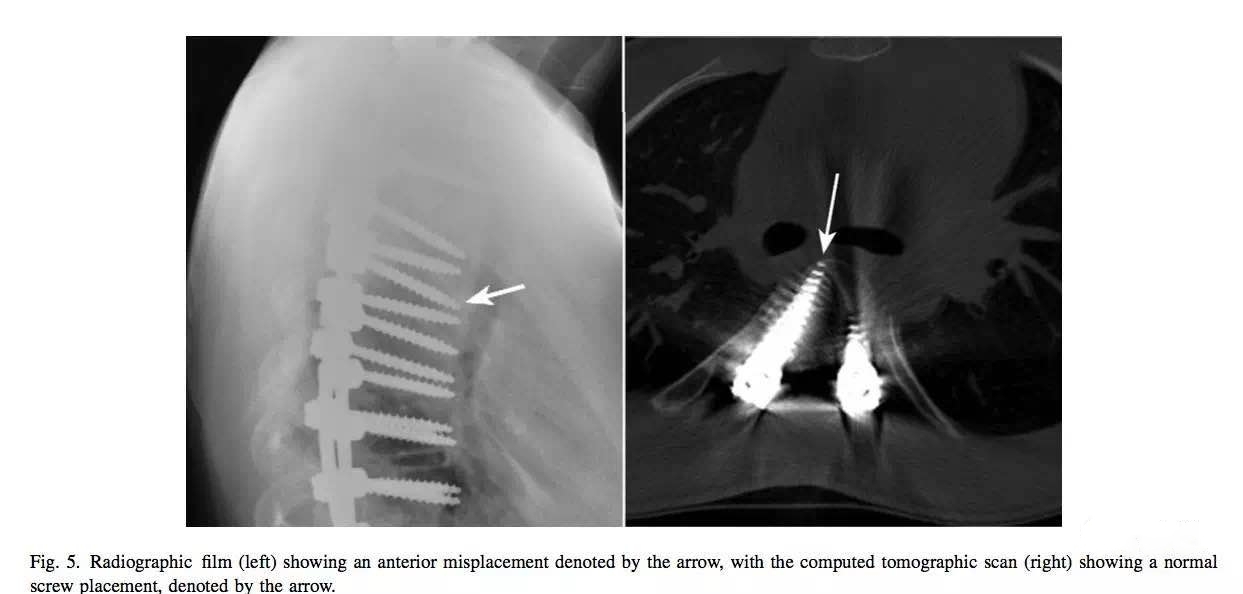

X线片显示钉尖超过棘突,钉道可能偏内进了椎管。但CT复查显示位置良好。

X线片显示钉道位置良好,但CT复查显示进了椎管。

X线片显示钉子可能偏外出去了,但CT复查显示钉道良好。

X线片显示钉道足够内倾,但CT复查显示钉子出去了。

X线片显示钉子太长,但CT复查显示钉子在椎体内。

术中C臂透视真的有时候做不得准。亲历过钉道怎么探查都很实,置钉后透视就是显示偏内在椎管,反复探查不得其法,最后打开椎管找到神经根直视下置钉,椎弓根内壁完好,C臂透视还显示钉道偏内。

还经常碰见术中透视、探查钉道都良好,术后复查CT钉子偏了。CT是判断置钉位置的金标准。